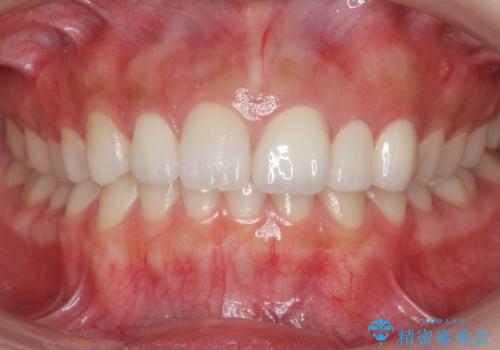

前歯が出っ歯ですきっ歯 抜かずに前歯を見た目良く

今回は左右とも1歯対2歯の関係であるため、それは変えずに前歯を可及的にひっこめて足りない部分をブリッジで補う治療としました。

矯正後の前歯ブリッジについては横浜桜木町歯科の大元院長が担当しています。

奥歯の関係を完全に1級にするには右上の小臼歯の抜歯が必要でしたが、もともと左上の前歯が生まれつき少ないため今回は歯を抜かずに治療しています。